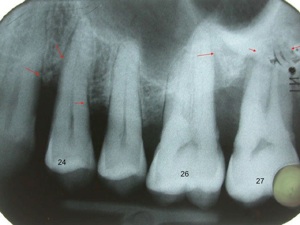

Parodontite = perte d’attache ( os , gencive, ligaments , cément radiculaire) , partiellement réversible par traitement non chirurgical ( détartrages et surfaçages radiculaires ) ou chirurgical et reprise correcte de l'hygiène dentaire et maintenance parodontale régulière . La perte osseuse horizontale est irréversible. On peut régénérer l’os partiellement dans le cas des lésions osseuses verticales.

2.Pour le parodonte épais, la résorption osseuse est accompagné par une faible récession gingivale et de la formation d’une poche parodontale

Dans les poches parodontales, les bactéries trouvent les conditions idéales pour se multiplier et sécrètent des toxines.

L’atteinte de la furcation interradiculaire est un facteur aggravant.

Résorption osseuse interradiculaire, classification des furcations:

Si la maladie parodontale n’est pas traitée l'évolution est vers la perte dentaire.

Pour certaines dents il faut prendre la décision d’extraction et remplacement par des implants , avant que la résorption osseuse soit trop avancée.